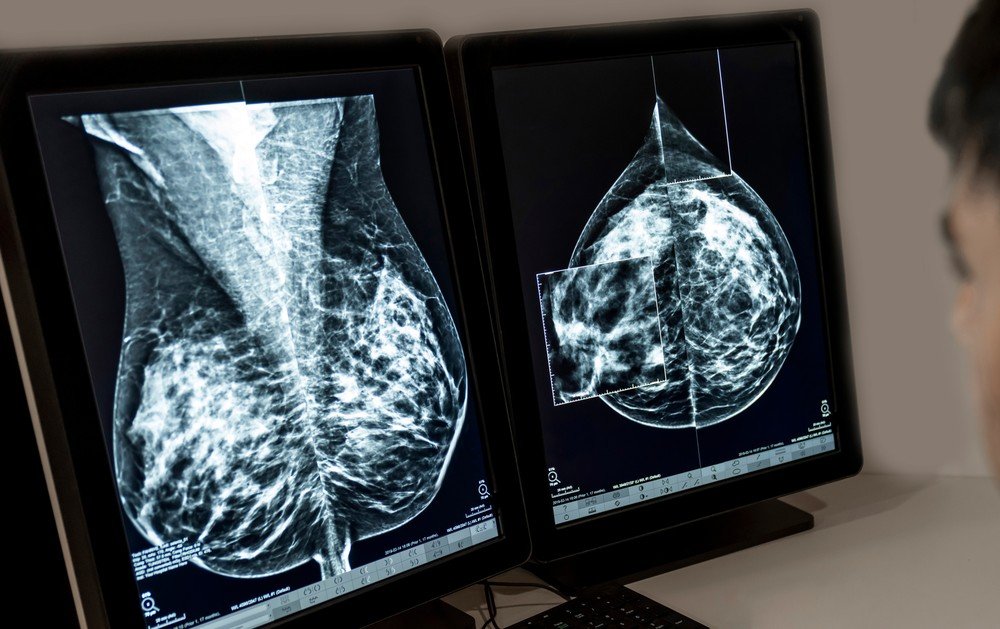

A interrupção dos exames de mamografia no Hospital Regional Jofre Cohen, em Parintins, tem gerado preocupação entre mulheres que dependem do serviço. De acordo com relatos de usuárias, o procedimento está suspenso desde o ano passado, deixando pacientes sem acesso a um exame essencial para o diagnóstico precoce do câncer de mama.

Márcia Baranda reforça que a mamografia é um instrumento fundamental na identificação precoce do câncer de mama, podendo reduzir a mortalidade e orientar tratamentos mais eficazes. A falta prolongada do exame, segundo ela, coloca em risco a saúde de centenas de mulheres que dependem do atendimento público. “É imprescindível garantir que as mulheres tenham acesso contínuo a um exame que pode salvar vidas”, destacou a vereadora.